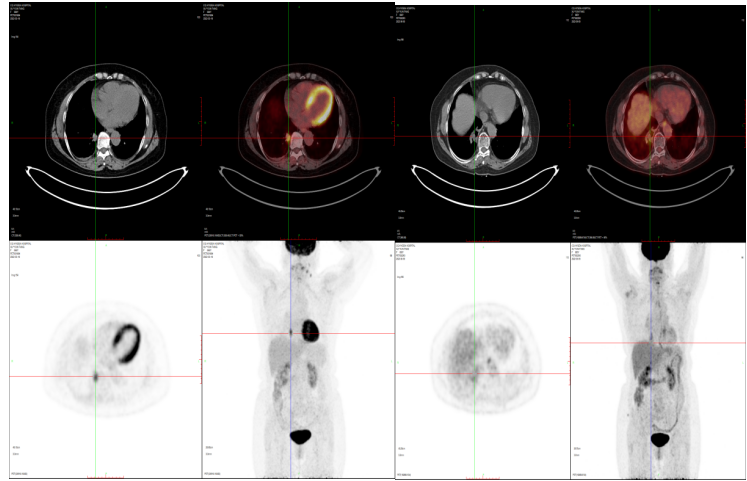

肺癌治疗后对比2022-3-18 2022-8-9